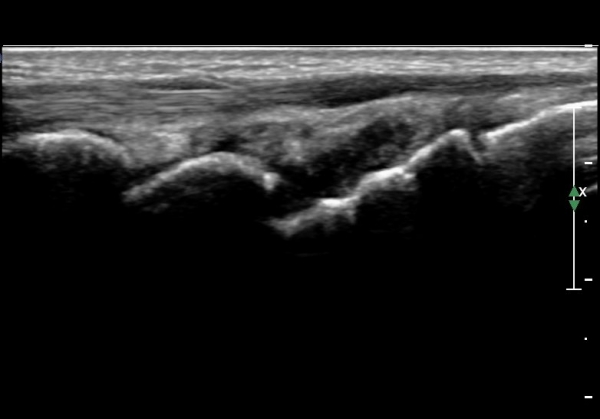

ÃÊÀ½ÆÄ°Ë»ç : ¼Õ¸ñ ¹èÃø Á¾´Ü¸é°Ë»ç¿¡¼­ ¼ö±Ù°üÀý³» ¼ö¾×Àú·ù°¡ °üÂûµÊ(»çÁø 1).

°í         Âû :  ¿Ü»ó ÈÄ °üÀý ºÎÁ¾ÀÌ ½ÉÇϰųª ±¹¼ÒÀû ¾ÐÅëÀÌ ¶Ñ·ÈÇÑ °æ¿ì¿¡´Â Ç×»ó °ñÀýÀÇ °¡´É¼ºÀ»

¿°µÎ¿¡ µÎ¼Ò ¹æ»ç¼±°Ë»ç »Ó ¾Æ´Ï¶ó ÃÊÀ½ÆÄ°Ë»ç¸¦ ¹Ýµå½Ã ½ÃÇàÇÏ¿© °ñÀý ¿©ºÎ¸¦

Á¤È®ÇÏ°Ô °¨º°ÇÏ´Â °ÍÀÌ ¸Å¿ì Áß¿äÇÏ´Ù.

¾î´À ºÎÀ§À̵ç ÃÊÀ½ÆÄ°Ë»ç¿¡¼­ °üÀý³» ºÎÁ¾ÀÌ °üÂûµÈ´Ù¸é ÀδëÆÄ¿­ ¶Ç´Â °ñÀý µî ½É°¢ÇÑ ¼Õ»óÀ»

¾Ï½ÃÇÏ´Â ¼Ò°ßÀÌ´Ù. µû¶ó¼­ ÃÊÀ½ÆÄ°Ë»ç»ó °ñÀý¼Ò°ß ¾øÀÌ °üÀý³» ºÎÁ¾ÀÌ °üÂûµÇ´Â °æ¿ì¿¡µµ °ñÀýÀÇ °¡´É¼ºÀ»

¿°µÎ¿¡ µÎ°í 1~2ÁÖ  ÃæºÐÈ÷ °íÁ¤ Ä¡·á ÈÄ ÃßÀû°Ë»ç¸¦ ½ÃÇàÇÏ¿© °ñÀý ¿©ºÎ¸¦ ÆÇ´ÜÇØ¾ß ÇÑ´Ù.